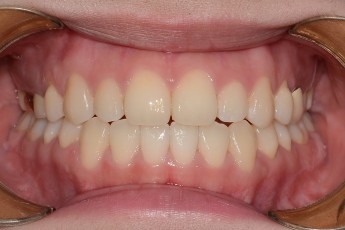

BEFORE & AFTER